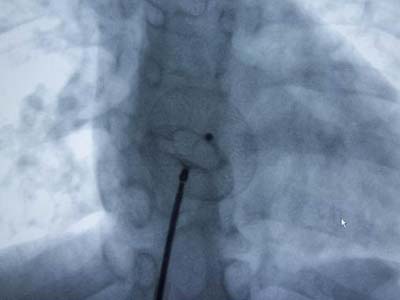

Carto三维定向标测系统指导下房颤射频消融术